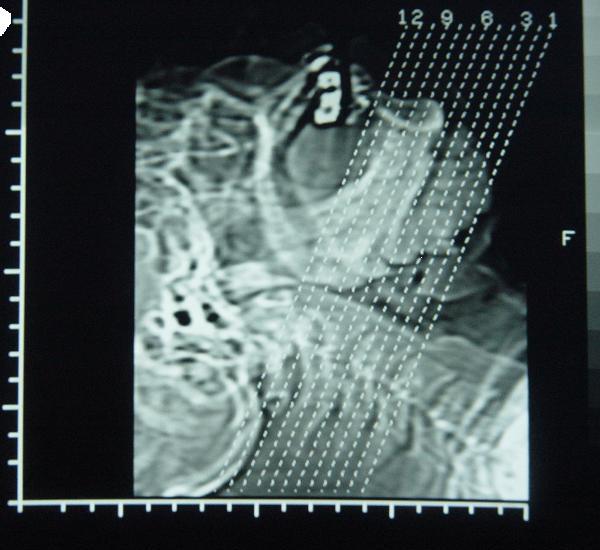

标题: CT12465:下颌骨肿瘤,请会诊 [打印本页]

标题: CT12465:下颌骨肿瘤,请会诊

发现下颌骨肿瘤近30年.逐渐增大.